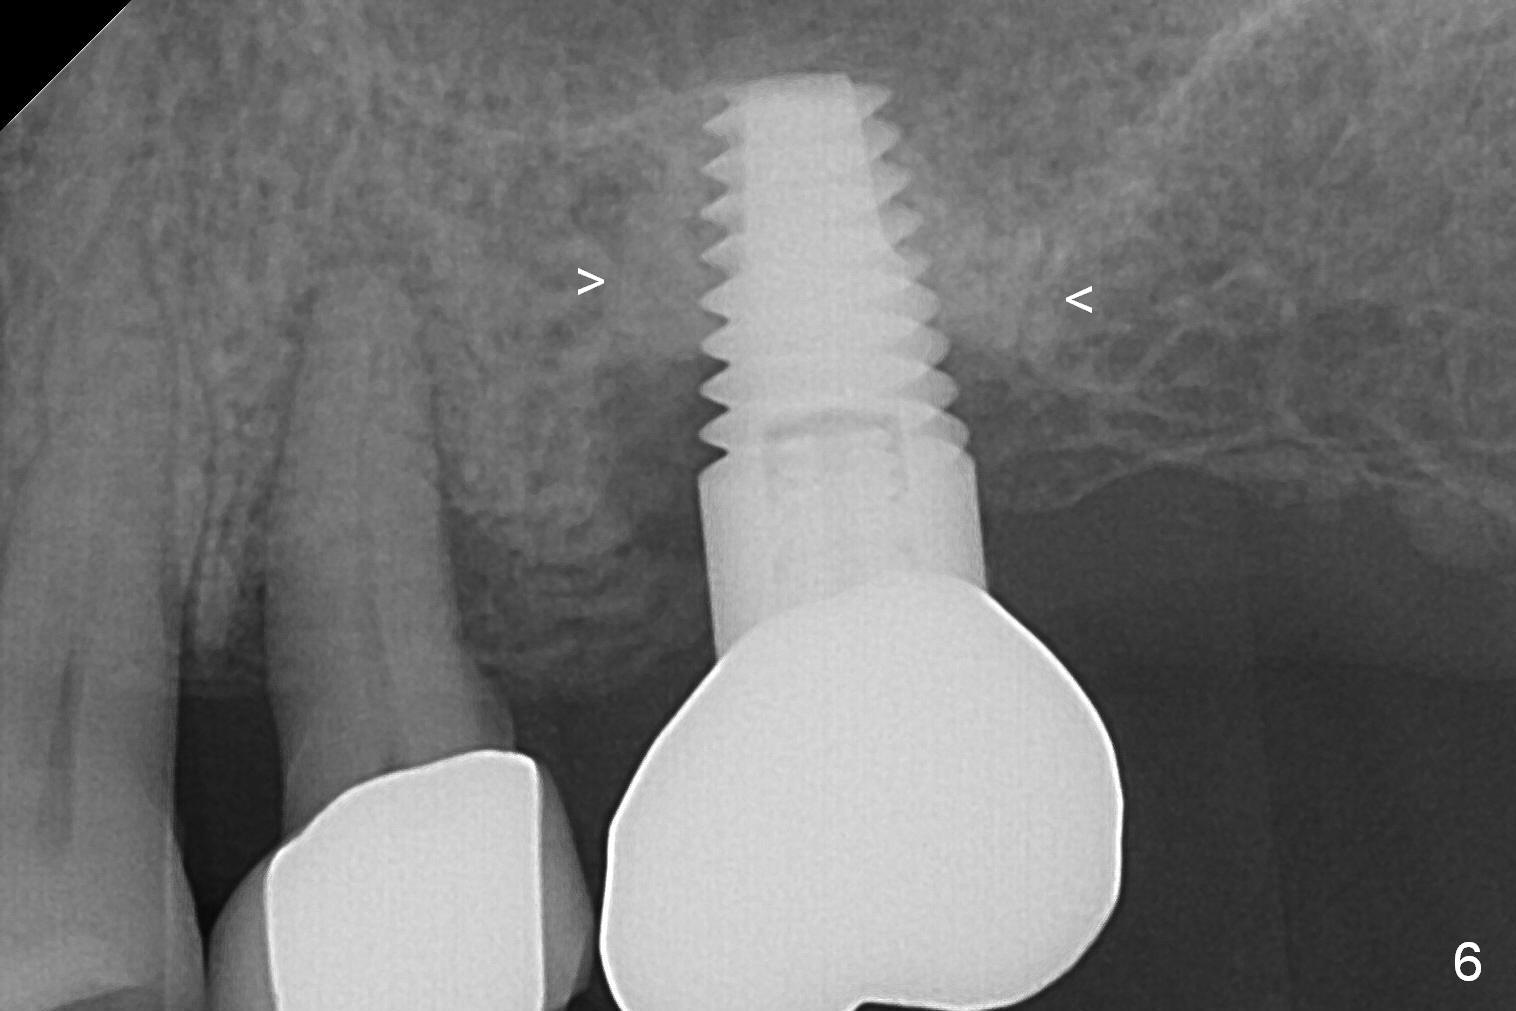

A 73-year-old woman is a possible bruxer with partial edentulism; the tooth #13 had increased periodontal ligament (pdl) space 4 years ago (Fig.1 *).  A 5x14 mm tissue-level implant is placed at the site of #14 (Fig.2).  The implant appears to be osteointegrated in 6 months (Fig.3).  There is crestal bone loss 8 months post cementation (Fig.4 *).  The persistent increased pdl at #13 is most likely associated with occlusal tramua from the tooth #19 (Fig.5 (13 months post cementation of #14)).  Three years post #14 cementation, the tooth #13 has mobililty II (Fig.6); bone density increases around the apical half of the implant (arrowheads).  Normally bone density is the highest coronally where functionality dictates.  This indicates the bone loss is getting worse at #14 as well.